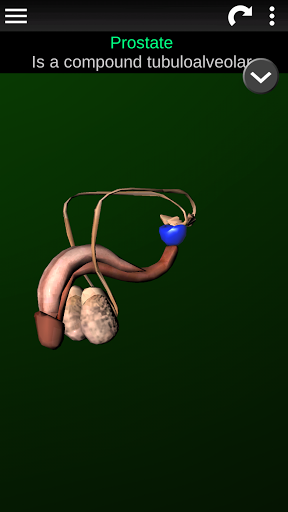

Internal Organs 3D Anatomy 3.4

Internal Organs 3D Anatomy 3.1

Organs 3D Anatomy 2.0.12